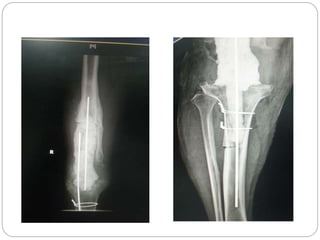

This document discusses 8 oncology cases. Case 1 involves a 40-year old female with right knee pain. Case 2 is a 28-year old male with a left subtrochantric fracture from a MVA who is now experiencing increasing left knee pain and swelling. Biopsy results showed high-grade osteosarcoma. Case 3 is a 30-year old female with breast cancer and bone metastases causing bilateral hip pain.